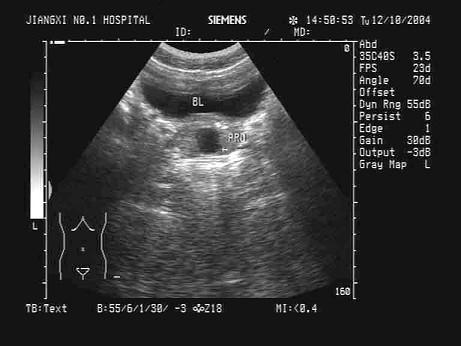

问题 某患者下腹部声像图表现,根据箭头提示,最可能的诊断为?(?)

选项 A.前列腺囊肿 B.膀胱憩室 C.前列腺癌 D.精液囊肿 E.膀胱肿瘤

答案 A